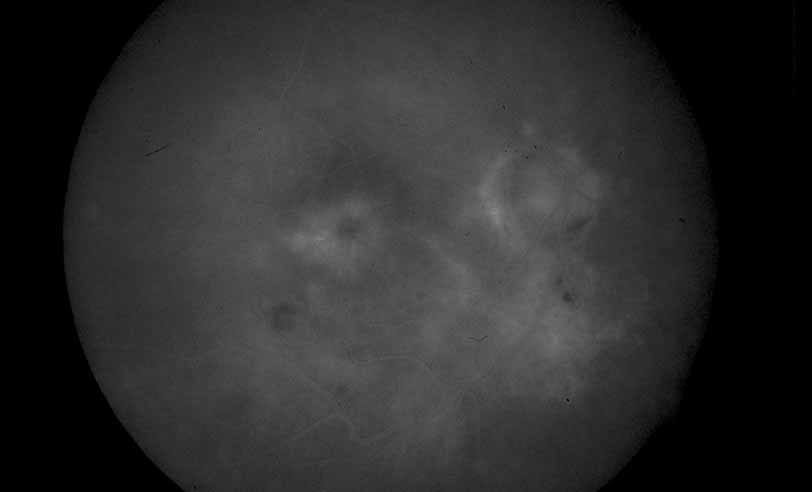

In addition to exudative detachment of the neurosensory retina and papillitis, patients with Vogt-Koyanagi-Harada disease as well as sympathetic ophthalmia may also develop serous detachment of the retinal pigment epithelium. This differs from the usual form of retinal pigment epithelium detachment that occurs in age-related macular degeneration by the absence of adjacent soft drusen and the presence of multiple pinpoint leak sites and disc staining characteristic of Vogt-Koyanagi-Harada disease (see Figs. 30, 31, 32, 33, and 34) and sympathetic ophthalmia (see Figs. 35 and 36).41–46 In cases of Vogt-Koyanagi-Harada disease with serous retinal detachment or detachment of the retinal pigment epithelium, some authors have reported hyperfluorescence of the large choroidal vessels in early stages of the angiogram, followed by dye leakage in the late phase of the study, whereas others report leakage from the choroidal vessels throughout the study (see Figs. 33 and 34).11,12

Fig. 33 Vogt-Koyanagi-Harada syndrome. Early ICG angiography shows hyperfluorescence of the large choroidal vessels in the central macula.

Fig. 34 Vogt-Koyanagi-Harada syndrome. Later frames of the ICG show a large plaque of hyperfluorescence.